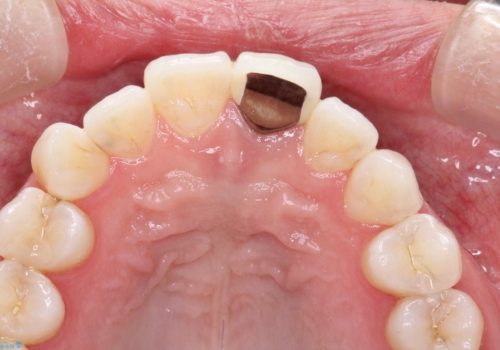

- 左上の前歯の形や色が気になる。

保険の前歯の被せ物のやりかえを希望して来院